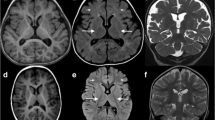

a Abnormal facial appearance; b hypoplasia of the corpus callosum and slightly wide sulci at bilateral frontal parietal lobes in brain MRI; c Sanger sequencing of MOGS mutations in the family in our study; d Conservation analysis of MOGS protein among different species. The position of the mutations at amino acids 540 and 565 is indicated by a blue bar and highly conserved throughout all indicated species; eMOGS RNA level was lower in peripheral blood of the patient compared with that of normal control. Both wide-type and mutated MOGS were expressed in Hela cells, and the mutant MOGS expression decreased, RNA level f, protein level g. P: patient, N, normal controls; WT, wild type. The results of three independent experiments are expressed as the mean + standard deviation (*P < 0.05; **P < 0.01)

Blood biochemistry examinations showed abnormal liver function with 55 U/L of glutamic-oxaloacetic transaminase (reference, 10~44 U/L), abnormal myocardial function with 255 U/L of CK (reference, 20~250 U/L), and 68 U/L of CK-MB (0~25 U/L), low immunoglobulin (13.7 g/L; reference, 20~40 g/L), impaired lipid metabolism with decreased HDL (0.75 mmol/L; reference, 0.9~1.74 mmol/L) and ApoA1(0.92 g/L; reference, 1.1~1.95 g/L), increased urine acid (562.7umol/L; reference, 90~420 μml/L). Blood sugar and thyroid function were normal. Echocardiography showed patent foramen ovale or atrial septal defect, electroencephalogram indicated atypic hypsarrhythmia. Brain MRI displayed thin corpus callosum and slightly wide sulci at bilateral frontal parietal lobes (Fig. 1b).

After examining the localization of mutated MOGS, we found that MOGS was co-localized with ER marker (PDI) (Fig. 2), indicating that these two mutations do not alter the cellular localization of MOGS protein.